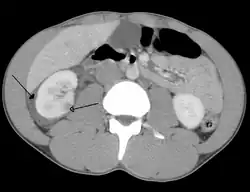

Spleen

Spleen is the most common cause of massive bleeding in blunt abdominal trauma to a solid organ. Spleen is the most commonly injured organ. A laceration of the spleen may be associated with hematoma.[13] Because of the spleen's ability to bleed profusely, a ruptured spleen can be life-threatening, resulting in shock. However, unlike the liver, penetrating trauma to the spleen, pancreas and kidneys do not present as much of an immediate threat of shock unless they lacerate a major blood vessel supplying the organs, such as the renal artery.[5] Fractures of the left lower ribs are associated with spleen lacerations in 20 percent of cases.[9]